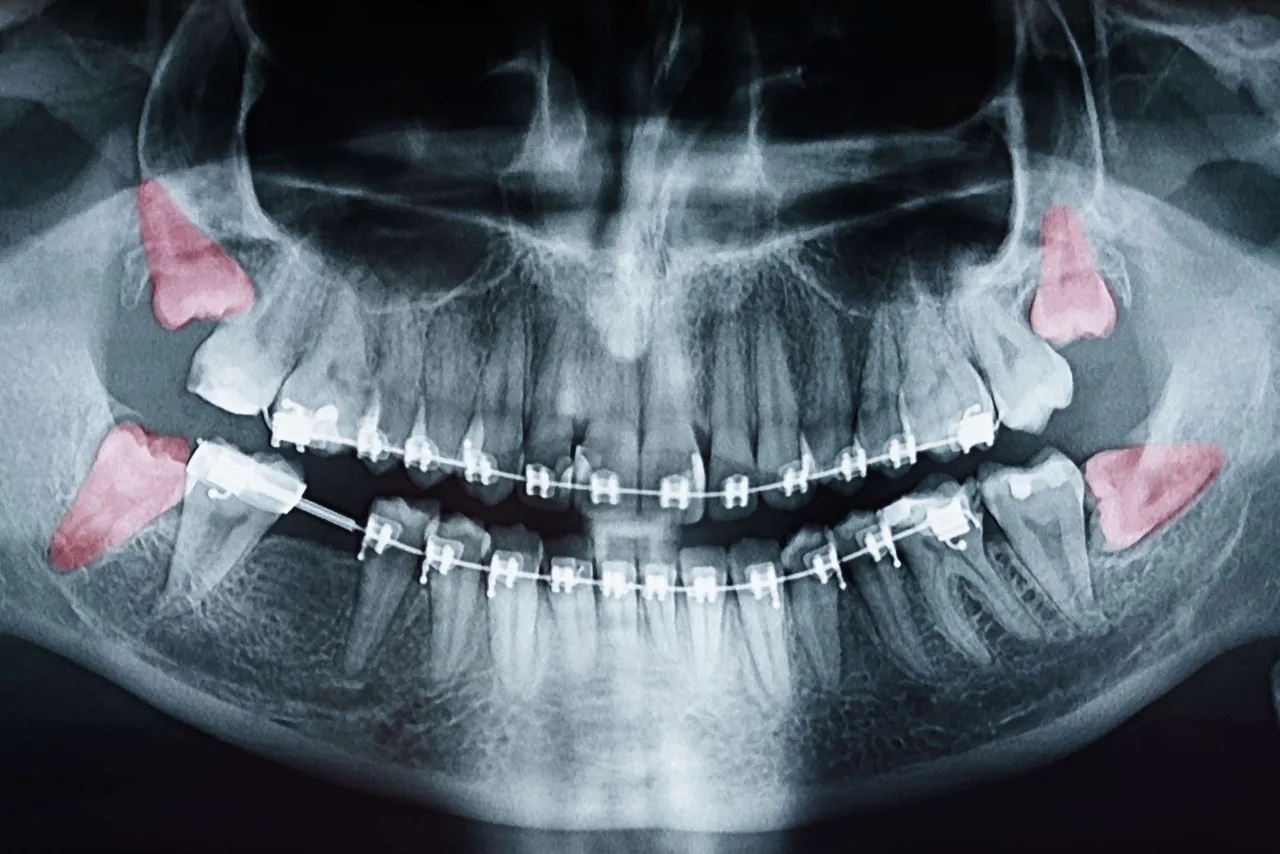

- Ekstrakcje zębów: Szczególnie skomplikowane usuwanie zębów mądrości (ósemek) oraz zębów zatrzymanych, które często wiąże się z dużym urazem tkanek.

- Zabiegi chirurgii stomatologicznej: Wszczepienie implantów zębowych, resekcje wierzchołka korzenia, usuwanie torbieli szczękowych czy inne inwazyjne procedury chirurgiczne w jamie ustnej.

Jednym z najczęstszych powodów do wystawienia zwolnienia lekarskiego przez dentystę jest ekstrakcja zęba, zwłaszcza skomplikowane usuwanie ósemki. Z mojego doświadczenia wynika, że te zabiegi są często inwazyjne i mogą prowadzić do znacznego bólu, obrzęku twarzy, trudności w jedzeniu i mówieniu, a nawet gorączki. Po takim zabiegu organizm potrzebuje czasu na regenerację, a praca, szczególnie fizyczna lub wymagająca intensywnego mówienia, może być niemożliwa do wykonania. W takich sytuacjach L4 jest w pełni uzasadnione, aby pacjent mógł spokojnie wrócić do zdrowia.

Inne zabiegi z zakresu chirurgii stomatologicznej, takie jak wszczepienie implantów zębowych, resekcje wierzchołka korzenia czy usuwanie torbieli, również często kwalifikują się do otrzymania zwolnienia lekarskiego. Są to procedury wymagające precyzji, często wiążące się z naruszeniem tkanek kostnych i dziąseł. Po ich wykonaniu pacjent może odczuwać ból, mieć obrzęk, a także wymagać stosowania leków przeciwbólowych i antybiotyków. Rekonwalescencja jest kluczowa dla prawidłowego gojenia i uniknięcia powikłań, dlatego zwolnienie jest w takich przypadkach standardową praktyką.